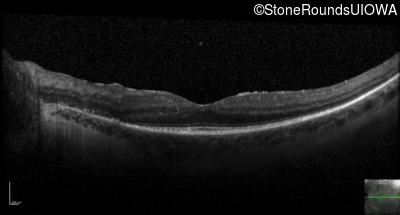

Optical Coherence Tomography - Left - 20/32 -1

Exemplar / OCT Stack